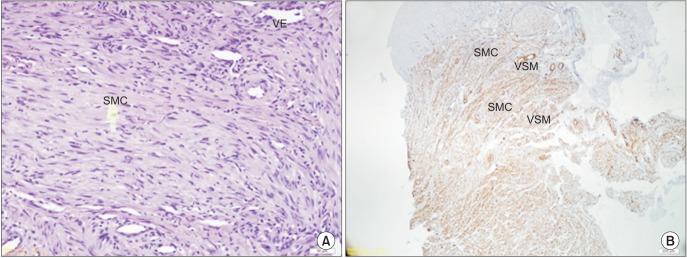

Leiomyoma is a type of benign smooth muscle neoplasm that is a common neoplasm of the uterus and gastrointestinal tract but rarely affects the head and neck region and is especially unlikely to affect the oral cavity. The diagnosis of leiomyoma is mainly determined by histopathological studies due to variation in its clinical appearance and symptoms. In the present paper we report two rare cases of gingival angioleiomyoma in the posterior maxilla and mandible. After total excision, hematoxylin-eosin and smooth muscle actin staining confirmed the diagnosis of angioleimyoma.